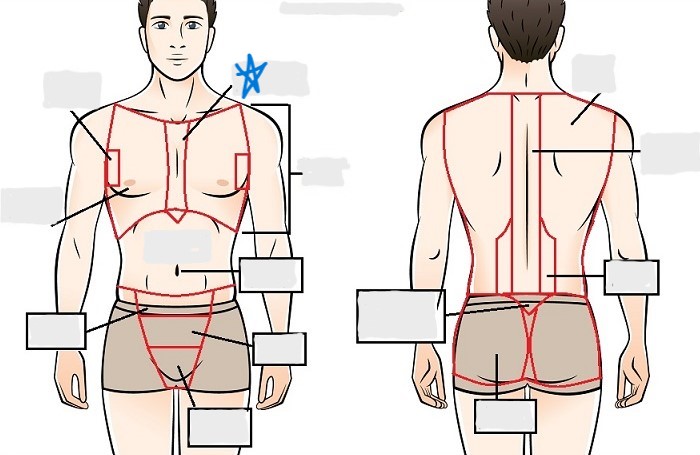

axial

cephalic

occipital

frontal

otic

orbital

nasal

oral

mental

cervical

dorsal

scapular

vertebral

lumbar

sacral

gluteal

thoracic

sternal

mammary

axillary

abdominal

umbilical

pelvic

inguinal

pubic

perineal

appendicular

acromial

brachial

antecubital

olecranal

antebrachial

carpal

manus

coxal

femoral

patellar

popliteal

crural

sural

peroneal

calcaneal

plantar